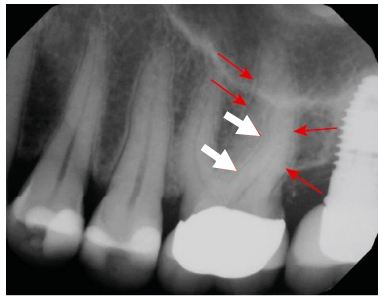

Com relação ao exame radiológico em endodontia, a imagem abaixo, de uma projeção periapical padrão, mostra os contornos da superfície radicular com o espaço do ligamento periodontal e a lâmina dura adjacente ao redor das raízes dos pré-molares e do primeiro molar, estruturas que o dentista deve visualizar para avaliar a saúde periapical. O que as setas brancas estão indicando?

(TORABINEJAD, Mahmoud; FOUAD, Ashraf F.; SHABAHANG, Shahrokh. Endodontia: princípios e práticas. 6. ed. Rio de Janeiro: GEN/ Guanabara Koogan, 2022. p. 45.)